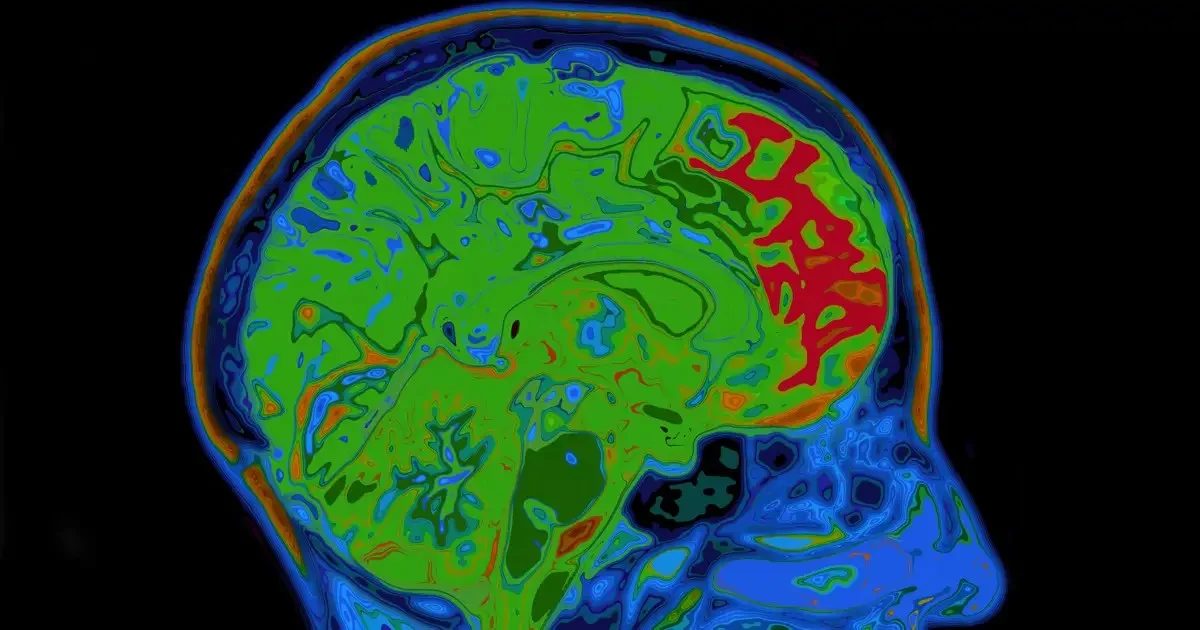

Forscher haben jetzt den neurobiologischen Mechanismus entdeckt, der blitzschnell entscheidet, ob eine Erfahrung im Hirn als „gut“ oder „schlecht“ abgespeichert wird. Es geht um eine Proteinkonstellation, die wir ignorieren, solange sie funktioniert. Wenn du das verstehst, kannst du endlich deine unerwünschten Routinen knacken.

Ein Forscherteam der Georgetown University Medical Center fand heraus, dass eine bestimmte Proteinaktivität im Gehirn wie ein mächtiger Beschleuniger für das sogenannte assoziative Lernen wirkt. Das ist der Prozess, der dafür sorgt, dass du nach dem Aufstehen zur Zahnbürste greifst – oder eben nach der Schokolade.

Dopamin ist unser Glückshormon und gleichzeitig unser Belohnungsbot. Weniger KCC2 bedeutet: Die Neuronen, die Dopamin ausschütten, werden *überdreht*. Das Gehirn verstärkt neue Verknüpfungen zwischen Umgebungssignalen (Kaffee) und Belohnung (Nikotin) explosionsartig.

Das Spannende ist die Synchronisation. Es geht nicht nur darum, *wie oft* Neuronen feuern, sondern *wie koordiniert* sie das tun. Synchrone neuronale Aktivität ist wie ein Chor, der perfekt singt – das führt zu einem massiven Dopamin-Stoß, der die Erinnerung zementiert.